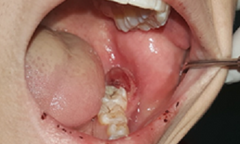

Bệnh viện Đại học Y Hà Nội đã xử trí thành công một trường hợp bệnh nhân bị u máu trong xương hàm doạ vỡ.